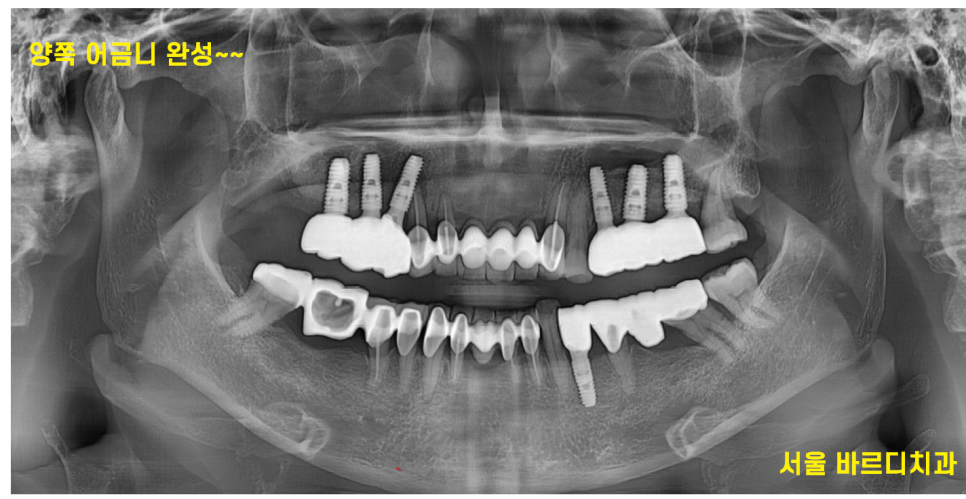

수술 후 6개월 뒤에 보철을 올렸습니다.

240809

임플란트 완성 사진입니다.

뼈이식을 하게 되면 치유기간이 길어지기 때문에

되도록 피하고 있습니다.

네비게이션 예측 , ct 분석 등을 통하여

정말로 어쩔 수 없는 경우에만 진행을 하고 있으니